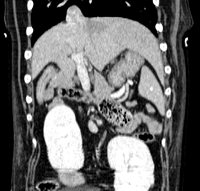

Abdomen & Pelvis

- Exploration des masses abdominales et pelviennes

- Bilan d'extension abdominal en cancérologie

- Exploration des organes abdominaux : foie, rate, pancréas, surrénales, reins...